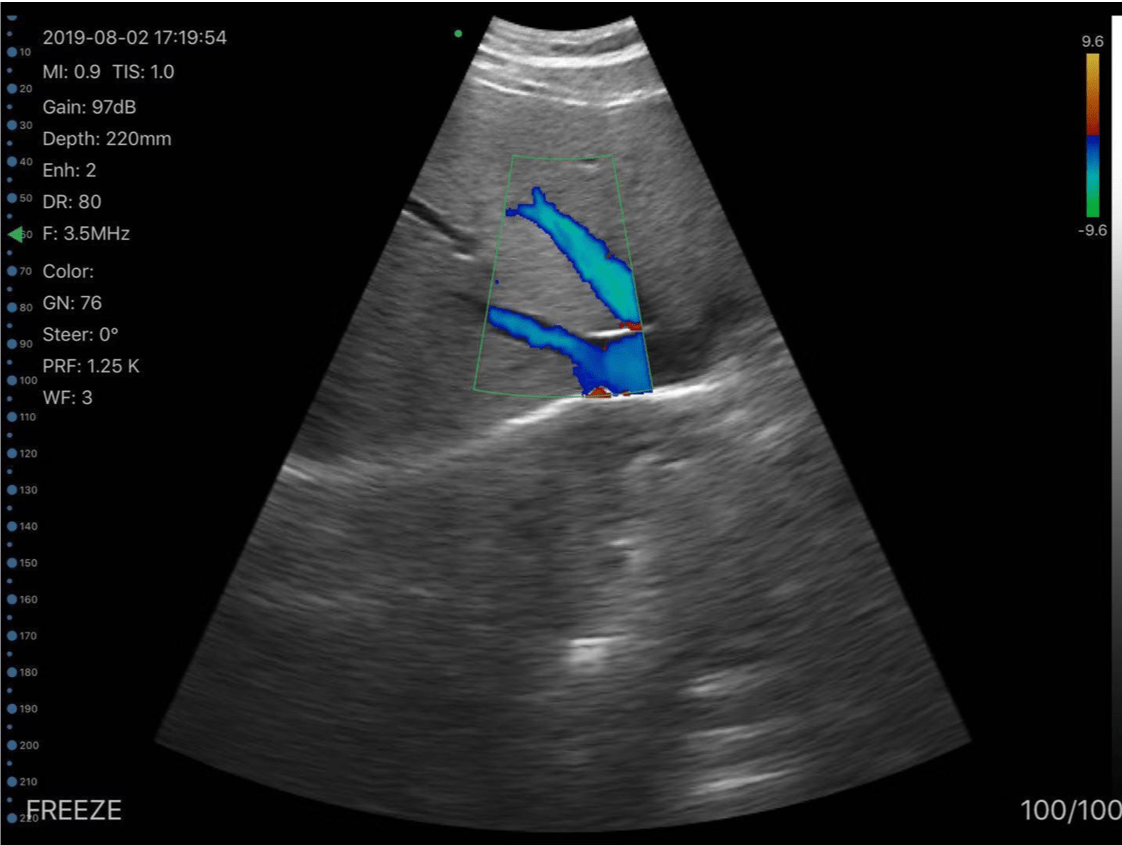

C10MT 3.5-5.0Mhz Convex B&W, Colour Portable Ultrasound.

The new C10MT Colour Doppler Hand Held Ultrasound probes with 128 element 24 frame per second frame rate gives real imaging performance for any application.

• Display mode: B, B/M, colour, PW, PDI

• Vassel Flow Preset(Auto Measure): PS,ED.TAMEAN,PI,RI,S/D, Diam, Flow